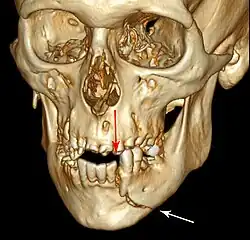

Computed tomography is the most sensitive and specific of the imaging techniques. The facial bones can be visualized as slices through the skeletal in either the axial, coronal or sagittal planes. Images can be reconstructed into a 3-dimensional view, to give a better sense of the displacement of various fragments. 3D reconstruction, however, can mask smaller fractures owing to volume averaging, scatter artifact and surrounding structures simply blocking the view of underlying areas.

3D CT reconstruction of mandible fracture, white arrow marks fracture, red arrow marks moderate displacement and open bite -

| 3D computed tomographic image of a mandible fracture in two places. One is a displaced right angle fracture and the other is a left parasymphyseal fracture. | |